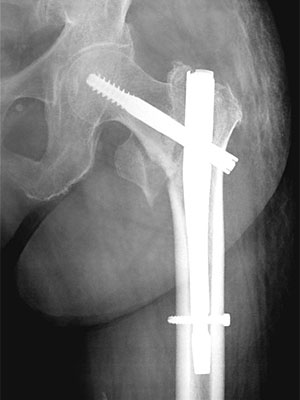

骨折後の手術例

股関節頚部外側骨折(γ-ネイル)